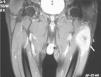

Se trata de un varón de 69 años, ex fumador, entre cuyos antecedentes personales destacaba la presencia de hipertensión arterial, dislipemia y polimialgia reumática. Consultó tras apreciar una tumoración en el muslo izquierdo de crecimiento lentamente progresivo, acompañada de un dolor sordo y continuo. Con excepción de una pérdida ponderal no cuantificada negaba otra sintomatología sistémica. Refería igualmente la aparición, al cabo de varias semanas, de una segunda lesión de menor tamaño en la pantorrilla derecha. La exploración física mostraba un paciente con buen estado general, sin hallazgos a la auscultación cardiopulmonar ni adenopatías palpables. Destacaba en la cara externa del muslo izquierdo una masa pétrea e indolora a la palpación (10×5 cm), con escasa movilidad en planos profundos, sin signos inflamatorios locales y cubierta de piel intacta, así como una segunda lesión (2×1 cm) de similares características en el gastrocnemio derecho. Una resonancia magnética (RM) con contraste puso de manifiesto una gran masa muy heterogénea de aspecto sarcomatoso en el músculo vasto externo del muslo izquierdo (fig. 1), y una masa de menor tamaño en el gastrocnemio lateral de la pierna derecha. Una citología obtenida de esta última lesión, mediante punción aspirativa con aguja fina (PAAF), fue congruente con un carcinoma pobremente diferenciado. Posteriormente, se realizó una biopsia incisional de la masa del muslo que confirmó la infiltración por un carcinoma epidermoide con fenotipo epitelial complejo en el estudio inmunohistoquímico (positividad para queratinas de alto peso molecular, panqueratinas AE1-AE3, trombomodulina, antígeno carcinoembrionario y p63). Se completó el estudio con una tomografía computarizada toracoabdominal que reveló múltiples nódulos pulmonares bilaterales indicativos de metástasis, entre los que destacaba una lesión en el vértice superior derecho de mayor tamaño (3×3,2 cm) y contornos espiculados que fue identificada como probable tumor primario. Mediante una PAAF transtorácica se obtuvo una muestra de cuyo estudio citológico fue compatible con un carcinoma escasamente diferenciado. Con el juicio de carcinoma pulmonar no microcítico (CPNM) en estadio IV, el paciente fue sometido a tratamiento quimioterápico con intención paliativa (cisplatino y docetaxel). A pesar de la disminución inicial del tamaño de las MME tras 6 ciclos de tratamiento, a los 10 meses se confirmó la progresión tumoral pulmonar, cerebral y hepática, optándose en ese momento por un manejo exclusivamente sintomático.